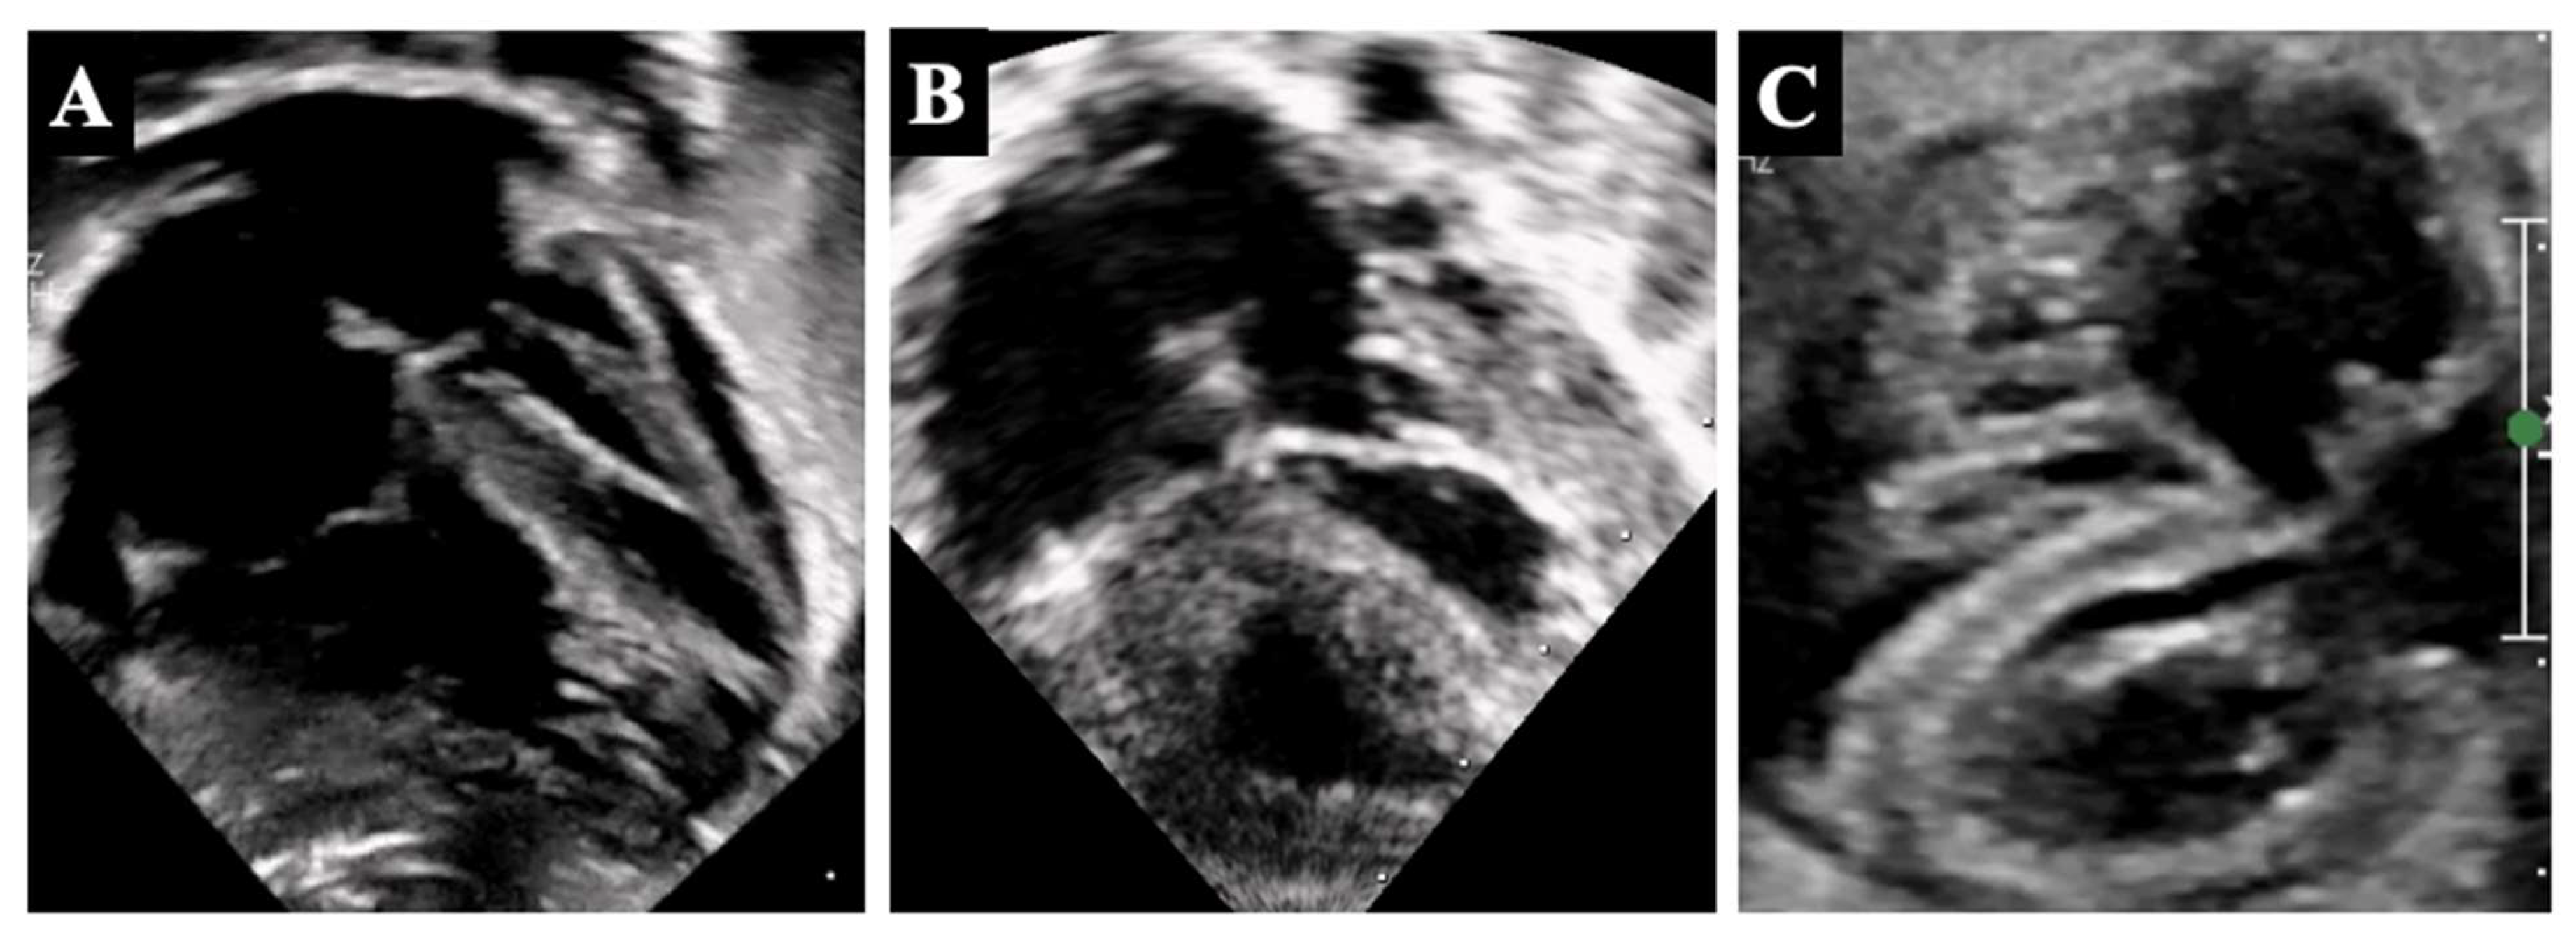

4. Borderline Right Ventricle: Predictors of Biventricular Repair

- The morphologic assessment of the RV (unipartite, bipartite, or tripartite) and the infundibulum (membranous vs. muscular pulmonary atresia);

- The assessment of the TV size, morphology, and function;

5.2. Borderline Right Ventricle